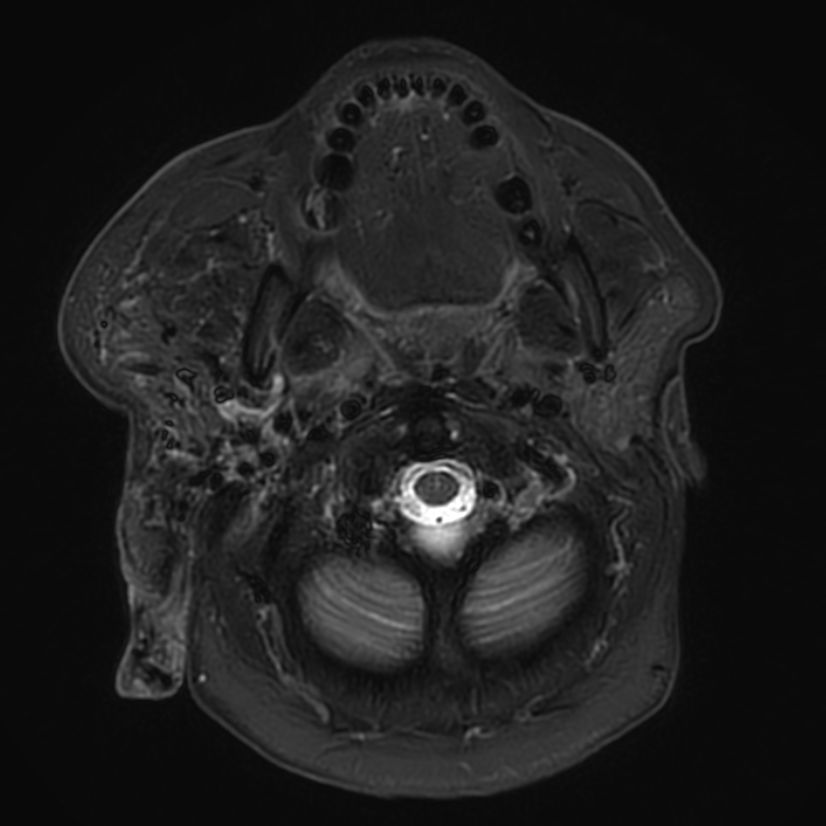

T1w TSE mDIXON XD (+gado) Compressed SENSE